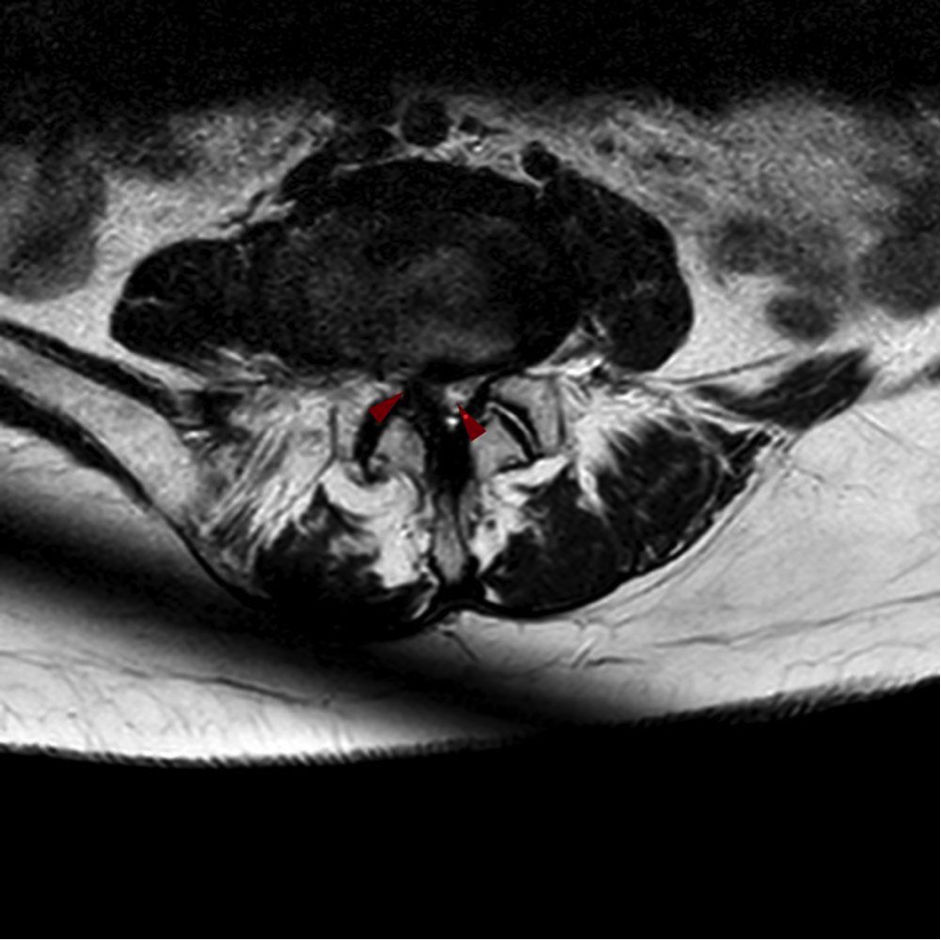

Καθοριστικό ρόλο παίζει ο απεικονιστικός έλεγχος, ο οποίος περιλαμβάνει την απλή ακτινογραφία, τη μαγνητική τομογραφία ή την αξονική τομογραφία. Η μαγνητική τομογραφία αποτελεί την εξέταση εκλογής, καθώς απεικονίζει με ακρίβεια τη συμπίεση του νωτιαίου μυελού ή των νευρικών ριζών. Σε περιπτώσεις όπου δεν είναι εφικτή η μαγνητική, μπορεί να πραγματοποιηθεί αξονική τομογραφία ή αξονική μυελογραφία. Ανάλογα με τα ευρήματα, η στένωση ταξινομείται σε κεντρική, πλάγια ή ενδοτρηματική, γεγονός που καθοδηγεί και την περαιτέρω θεραπευτική προσέγγιση.